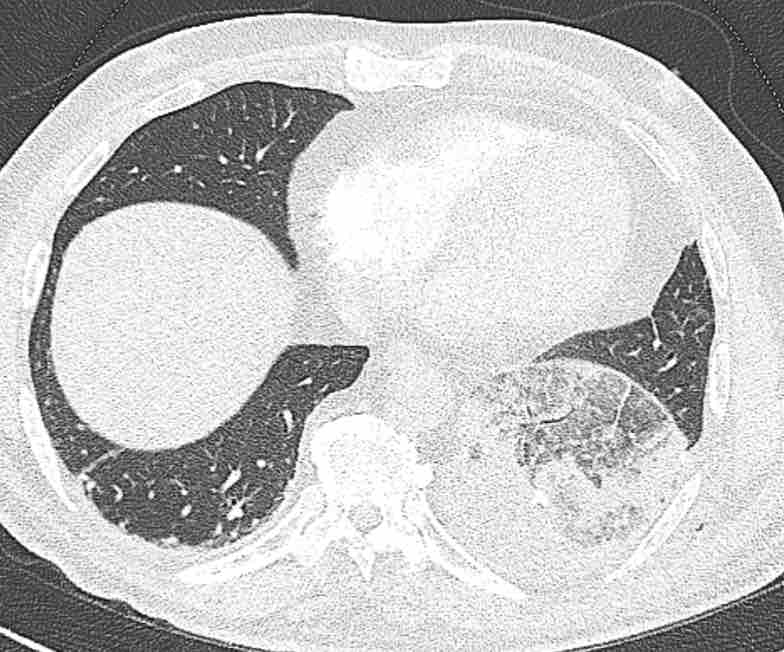

Theo dõi các phế quản của thùy dưới phổi trái cho thấy nhánh phân thùy đầu tiên của thùy dưới phổi trái còn thông; đó là phế quản phân thùy đỉnh.

Các ghim phẫu thuật nằm tại vị trí của các phân thùy đáy sau và đáy bên (LB9/10), vốn thường được cắt bỏ cùng nhau.

Do đó, phân thùy phổi có hình ảnh kính mờ và đông đặc phải là phân thùy đáy trước của thùy dưới phổi trái (LB8).

Động mạch phổi đến phân thùy này cũng không ngấm thuốc cản quang, và bản đồ tưới máu iốt nhấn mạnh thêm tình trạng nhồi máu.

Bệnh nhân đã được phẫu thuật lại và tiến hành cắt bỏ phân thùy bị nhồi máu, với xác nhận qua giải phẫu bệnh.

Tiếp tục với bản đồ tưới máu…

Trên bản đồ tưới máu iốt, có sự tưới máu ở thùy trên phổi trái và phân thùy đỉnh của thùy dưới phổi trái, nhưng không có sự tưới máu ở phân thùy đáy trước của thùy dưới phổi trái.